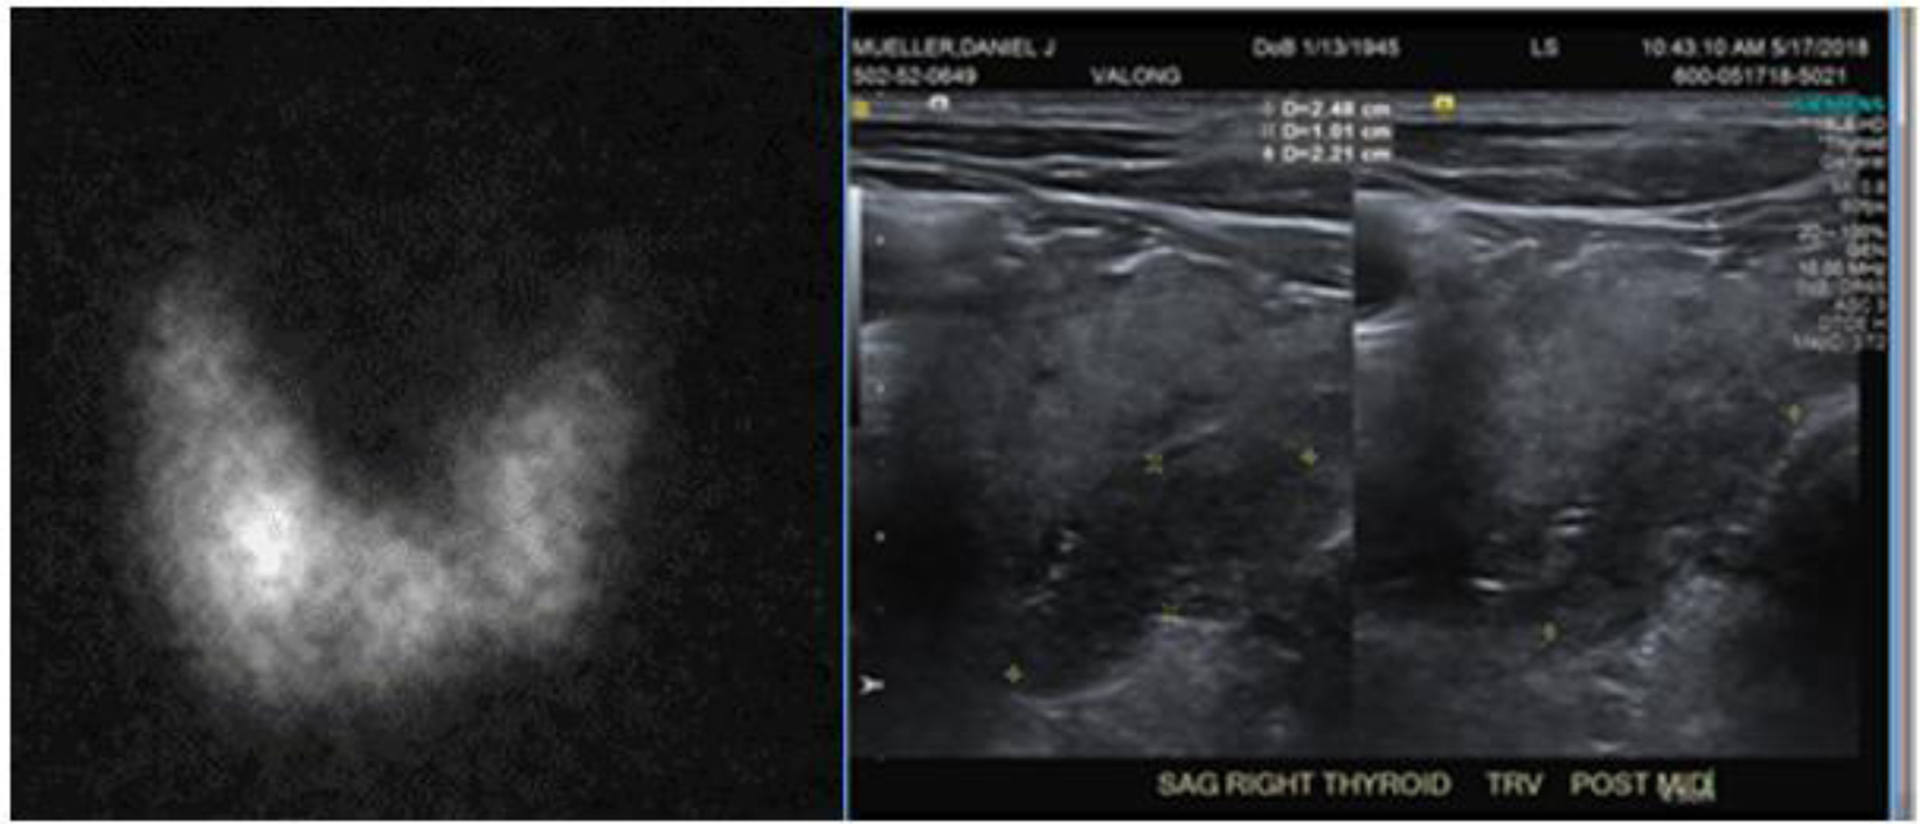

Abstract Image